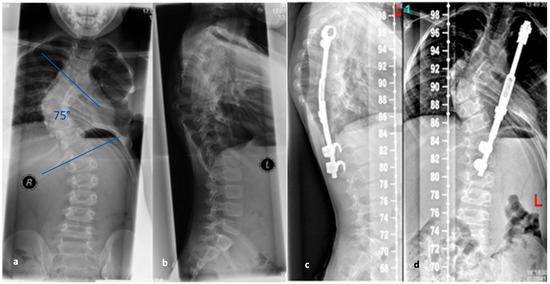

Figure 5. (a,b). Initial radiographs of a patient with adolescent idiopathic scoliosis. (c,d). Bending radiographs. (e,f). Postoperative image displaying implanted magnetically controlled growing rods as a dual rod system. (g,h). The patient was treated with a spondylodesis upon the completion of growth to maintain correction success (Reprinted with permission [10]).